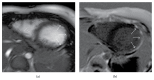

The use of psychostimulants labeled to treat attention deficit/hyperactivity disorder increases. Among side effects these drugs raise blood pressure and heart rate, and the safety has been scrutinised in recent years. Data from large epidemiological studies, including over a million person-years, did not report any cases of myocardial infarction in current users of methylphenidate, and the risk of serious adverse cardiac events was not found to be increased. We present a case with an 11-year-old child, treated with methylphenidate, who suffered cardiac arrest and was diagnosed with a remote myocardial infarction. This demonstrates that myocardial infarction can happen due to methylphenidate exposure in a cardiac healthy child, without cardiovascular risk factors.